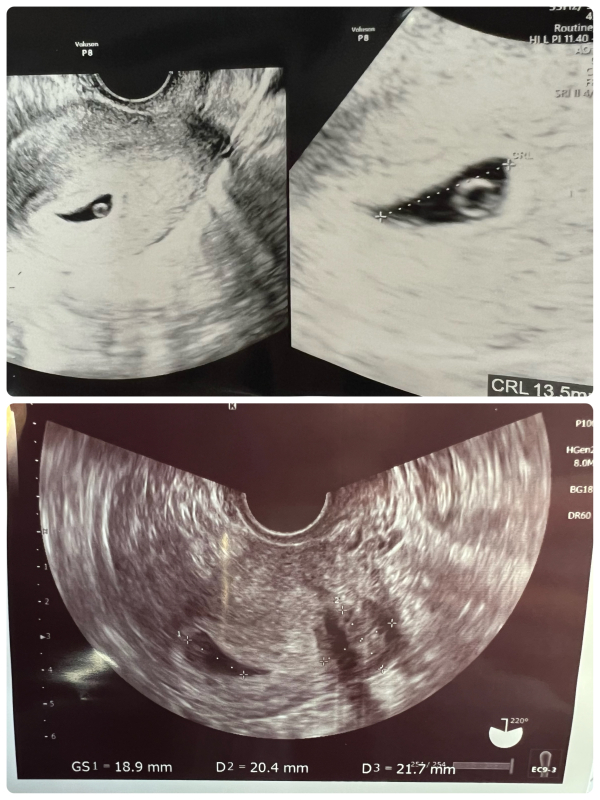

6週1日エコー 見えていた卵黄嚢が見えなくなった

胎嚢は5ミリほど大きくなって確認できましたが

中に何も確認できませんでした。

先生はチラチラうつっているのがそうなのじゃないかと仰っていましたが、私には全くわかりませんでした。

あと子宮底部の方にあるので角度的に見えづらい場所とおっしゃっていましたが、そうだとしてもあんなにはっきりと見えていた卵黄嚢がこんなに見えなくなるものなんでしょうか。。

胎嚢の形もまんまるではないので不安が募るばかりです。

写真の上が1回目のエコーで、下が2回目のエコーです。